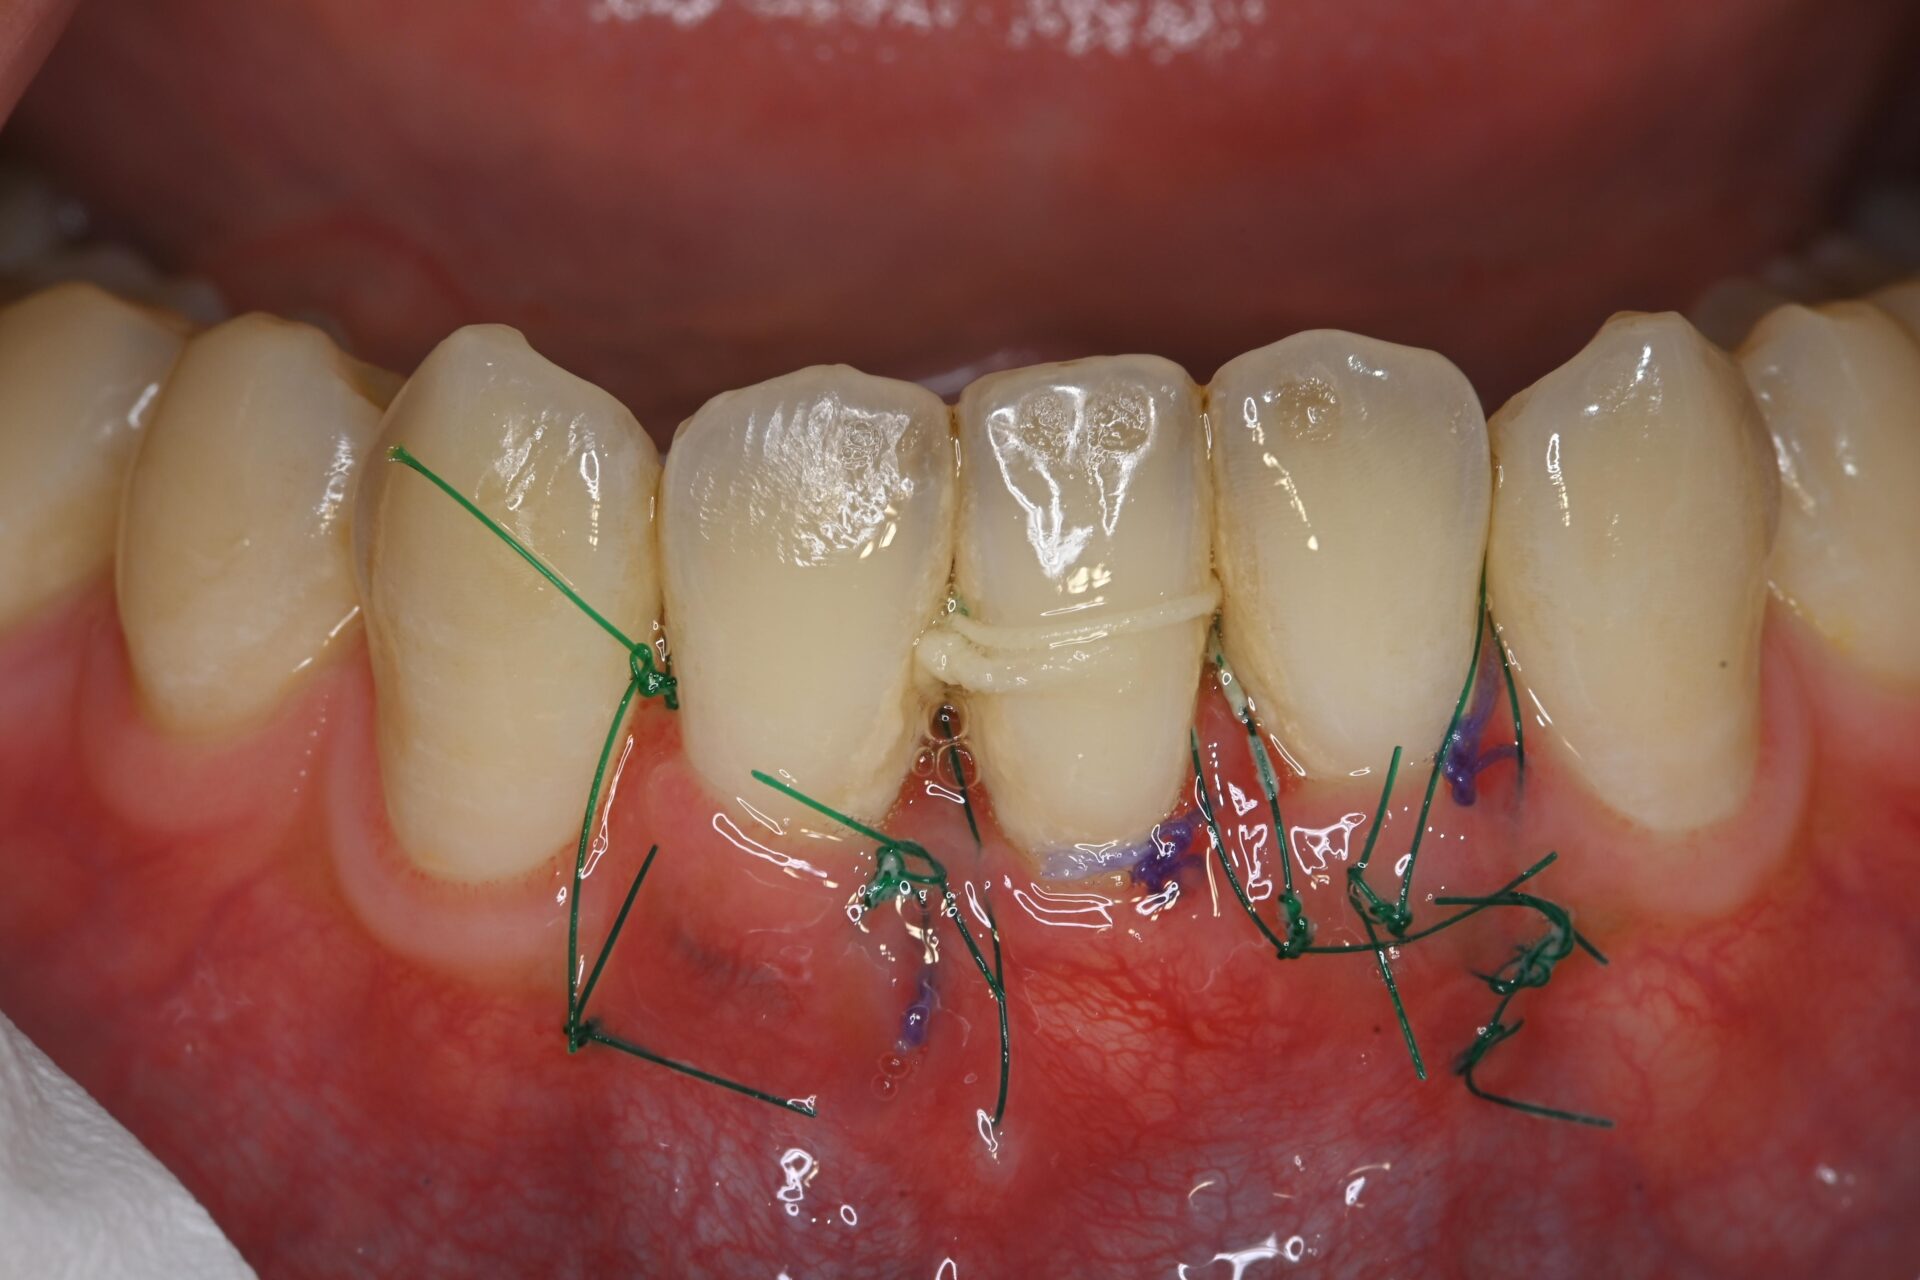

CTG(結合組織移植術) 臨床例②

矯正治療後、下顎前歯部の歯肉が退縮して歯根が露出し、見た目と機能の両面でお悩みでした。歯肉は非常に薄く、付着歯肉も不足しており、ブラッシング時に傷つきやすく、清掃が困難な状態でした。そのため、炎症を繰り返しており、審美的にも不均衡が見られました。長期的に歯周組織を安定させるには、外科的な介入が必要と判断しました。

術前